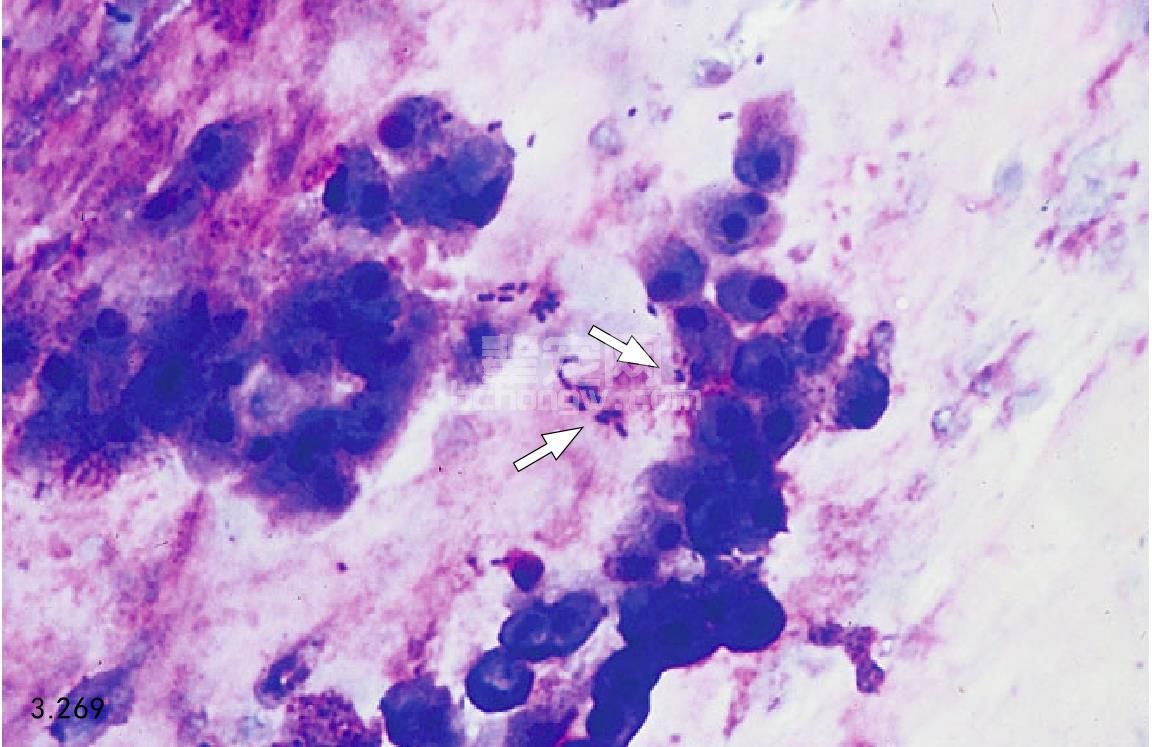

外科治疗 动物急性胰腺炎手术时,有几个重要注意事项:治疗潜在性的可行疾病,如胰腺假性囊肿或脓肿;消除最初胰腺炎疾病;在出血性坏死胰腺炎的败血性阶段,应切除坏死或感染病灶;纠正并发症如胆管阻塞(图3.269~图3.274)。

图3.269 急性胰腺炎手术的显示之一为胰腺蜂窝织炎和继发性细菌感染。此犬患有明显胰腺蜂窝织炎坏死和脓肿形成,取腹腔液检验其细胞。图中可见中毒性中性粒细胞中含有细菌,细胞外有游离细菌(箭头所指)。发生感染细菌培养时,多常见革兰阴性菌。